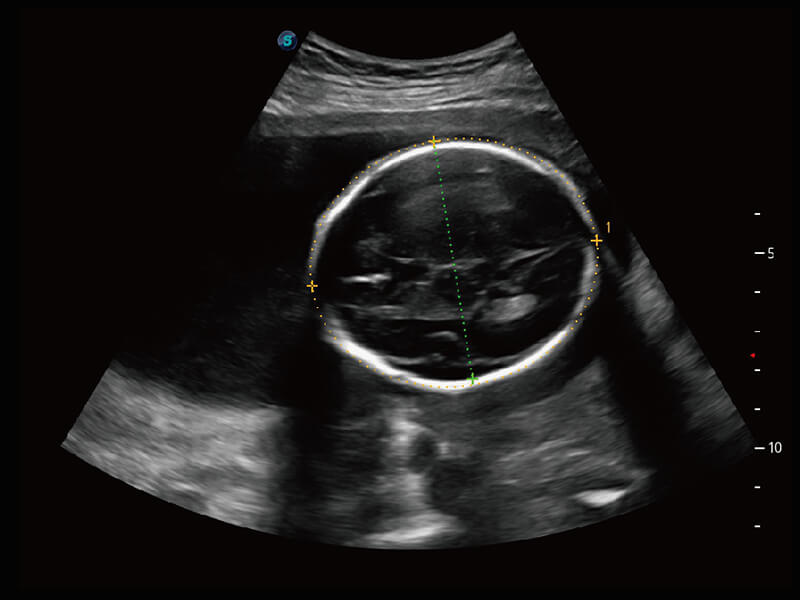

高分辨率容积成像 栩栩如生

超宽频带技术,为容积成像带来优质的二维图像基础,为您呈现丰富的结构细节,栩栩如生地展示宝宝的宫内形态以及各种组织的立体结构。